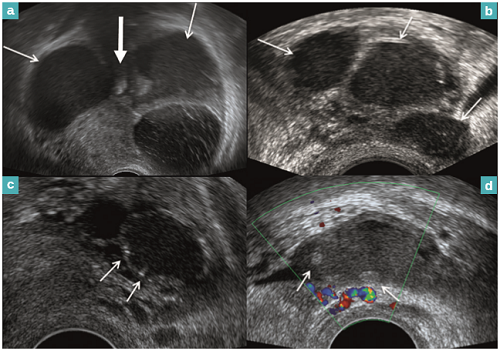

Endométriose, apport de l’échographie endovaginale.

L’endométriose est une maladie bénigne touchant 10 à 15% des femmes en âge de procréer. Elle est définie par la présence de tissu endométrial en dehors de la cavité utérine. Il existe trois formes cliniques plus ou moins associées : l’endométriose superficielle, les kystes ovariens ou endométriomes, et l’endométriose profonde. Les principaux signes cliniques sont les dysménorrhées, les dyspareunies et les douleurs pelviennes chroniques. Elle est également source d’infertilité. L’imagerie par échographie endovaginale et par résonance magnétique est souvent nécessaire pour établir le diagnostic. Dr Bounhir BOUMEHDI, exposera les dernières données radiologiques sur l’endométriose, présentées discutées lors du congrès internationale de l’imagerie médicale/ Paris 13 au 17 octobre 2016, en se posant la question suivante, cette technique est-elle suffisamment développée au Maroc ?